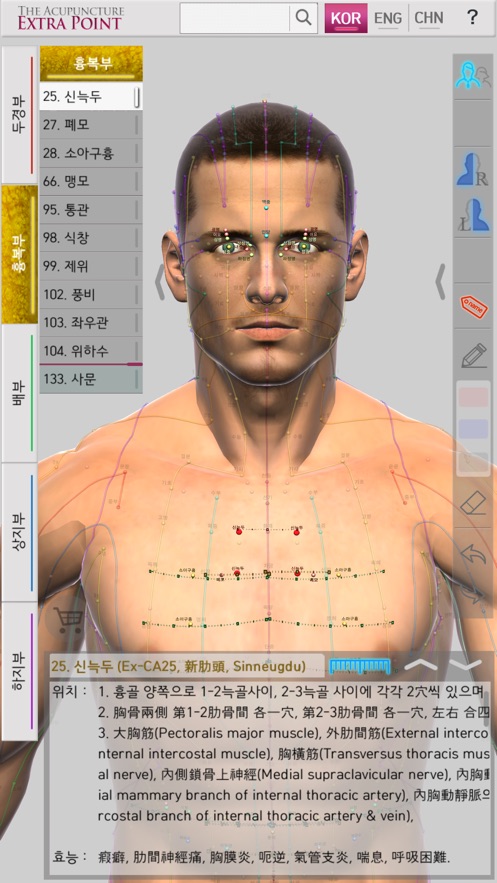

‘The Acupuncture of Extra Point’ was created by integrating Extra Point from the past, and the newly discovered New Point together as one product. It allows for easy comparison because it expresses 14 Main Acupuncture Point Meridian and the Extra Acupuncture Point together in a male and female 3D model. Easily zoom in and out with multi-touch so you can see the exact location of The Acupuncture Point. It is recommended for people who want to see both 14 Main Acupuncture Point Meridian and the Extra Acupuncture Point at the same time. Contents include accurate location, based book, function and character (how to use). Released in Korean, Chinese and English, which allows it to be used across the world! With realistic skin, bone, and internal organs in 3D human body model, everything is distinguished by rich colors so it is very easy to see. It is based on The International Standard Acupuncture Points of WHO, WHO`s International Standard Terminologies on Traditional Medicine in The Western Pacific Region, The acupuncture textbooks of the university of Asian Medicine and 'Huangdi Neijing - Lingshu’. It is supervised by professors and Korean medical doctors from Korea Medical University. * 14 Main Acupuncture Point Meridian - 12 Main Acupuncture Point, Governor Vessel (GV) Acupuncture Point, Conception Vessel(CV) Acupuncture Point.- See The Meridian 2.0

‘The Acupuncture of Extra Point’ is the only product in the world that expresses the Extra Acupuncture Point on male and female 3D human models.

‘The Acupuncture of Extra Point’ is easy to use because it displays The Extra Acupuncture Point on 3D human body model. As well, the Extra Acupuncture Point and 14 Main Acupuncture Point Meridians are displayed together with the accuracy, so you can easily compare.

In 'The Acupuncture of Extra Point’, the skin, bones, and internal organs of the 3D human model look realistic. The 14 Main Acupuncture Point Meridians and the Extra Acupuncture Point are distinguished by rich colors so they are very easy to see.